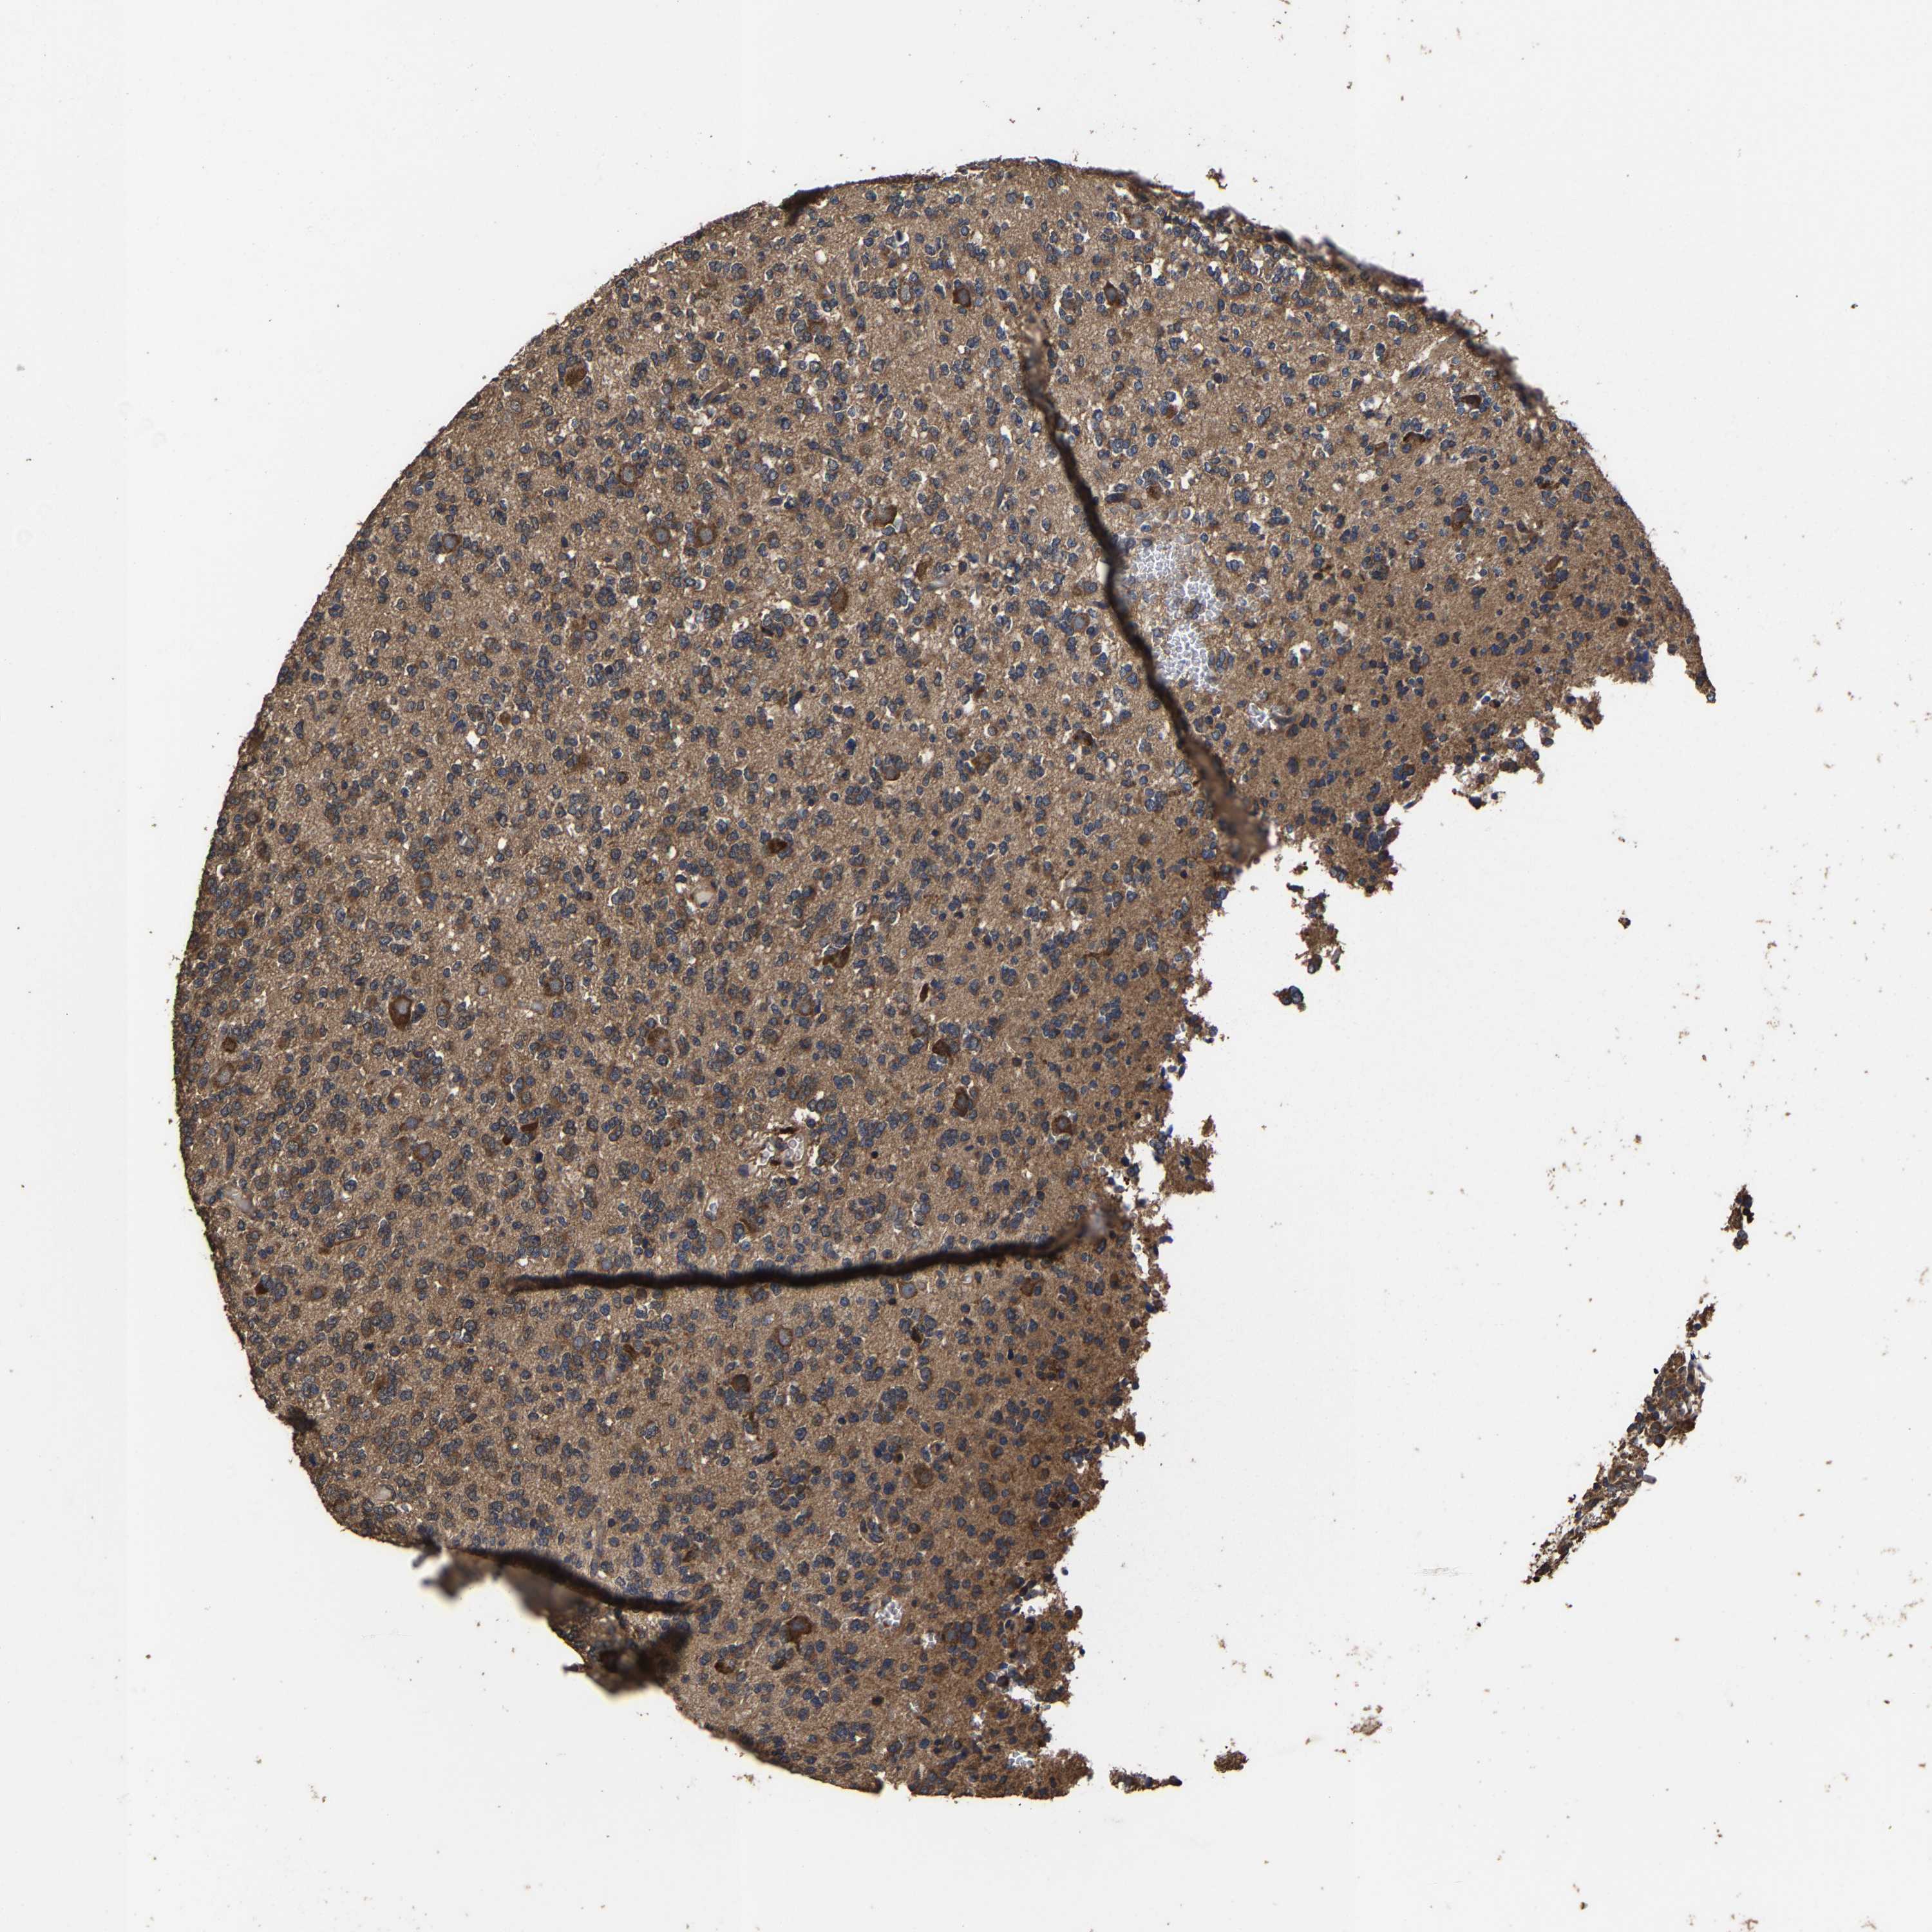

GLIOMA - Protein expressioni

A mouse-over function shows sample information and annotation data. Click on an image to view it in a full screen mode. Samples can be filtered based on level of antibody staining by selecting one or several of the following categories: high, medium, low and not detected. The assay and annotation is described here.

Note that samples used for immunohistochemistry by the Human Protein Atlas do not correspond to samples in the TCGA dataset.

Antibody stainingi

Antibody staining in the annotated cell types in the current human tissue is reported as not detected, low, medium, or high, based on conventional immunohistochemistry profiling in selected tissues. This score is based on the combination of the staining intensity and fraction of stained cells.

Each image is clickable and will lead to virtual microscopy that enables deeper exploration of all samples and also displays staining intensity scores, fraction scores and subcellular localization as well as patient and tissue information for each sample.

Antibody HPA021126

Staining

High

Medium

Low

Not detected

Intensity

Strong

Moderate

Weak

Negative

Quantity

>75%

75%-25%

<25%

None

Location

Nuclear

Cytoplasmic/membranous

Cytoplasmic/membranous,nuclear

Glioma, malignant, High grade

Glioma, malignant, Low grade